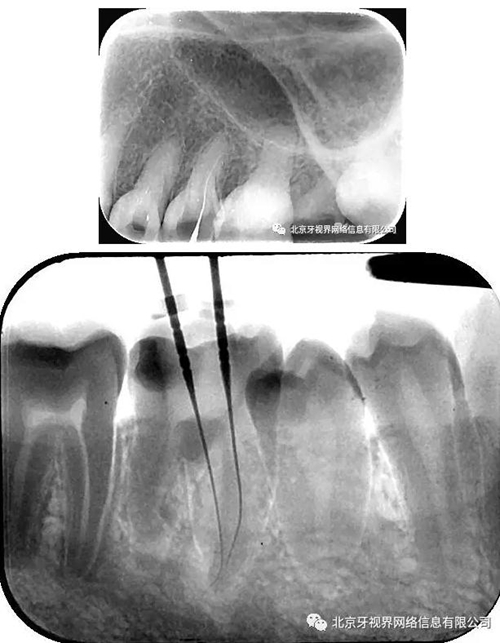

輔助檢查:15根尖周低密度影像,根尖1/3向近中彎曲

(1)15根尖周低密度影像結(jié)合查體診斷根尖周炎,根尖中下段明顯彎曲,能否疏通全長(zhǎng),順利抵達(dá)根尖區(qū)為術(shù)者首要考慮。

(3)彎曲根管的定義:Schneidre法測(cè)量

直根管(0度)中度彎曲(10-25度)重度(25-70度)

2.如遇彎曲根管,建議多角度拍攝x線片,cbct首選

4.此例病例中,術(shù)前分析后,采取先解放其中上段后,10#擴(kuò)大器預(yù)彎緩慢前行,抵達(dá)根尖區(qū)。

最后附帶近期彎曲根管的圖片